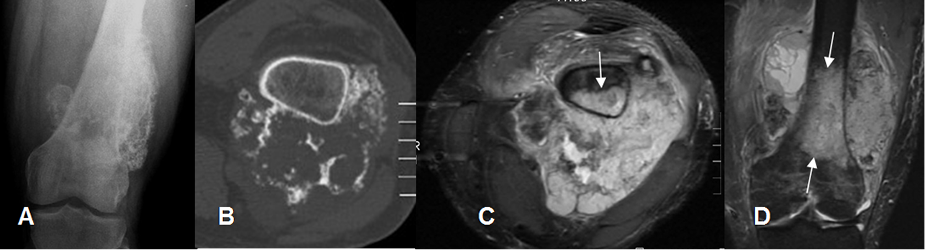

Fig 71 A. Osteosarcoma.

A: Rx AP y B: TAC axial. Lesión expansiva de comportamiento maligno y origen cortical.

C: RM axial en STIR y D: RM coronal en STIR. También se encuentra compromiso medular

y gran masa heterogénea de tejidos blandos, por osteosarcoma.